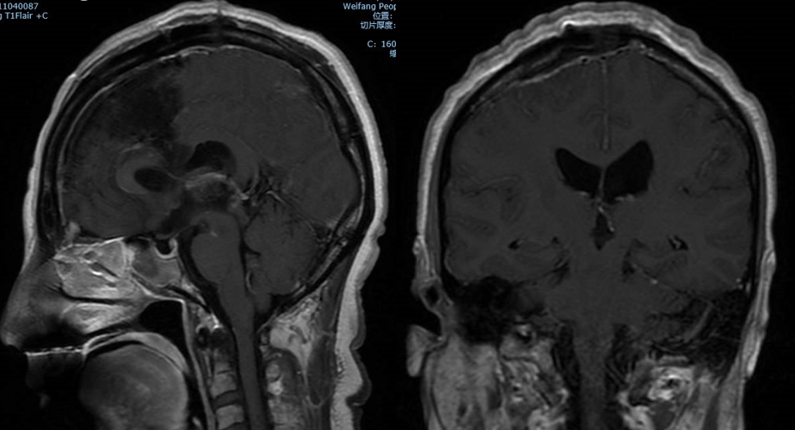

中年女性,因“头痛伴记忆力减退1月” 入院;

查体:神志清醒,反应迟钝,精神差,高级认知功能差,双下肢肌力IV级;

诊断:三脑室占位,梗阻性脑积水。

诊治过程:结合患者临床表现及影像学表现,初步诊断考虑为三脑室后部胶质瘤合并梗阻性脑积水可能性大,术前制定的手术方案为经胼胝体穹隆间入路三脑室后部肿瘤切除术+脑室镜辅助下三脑室底造瘘术,该手术方式既可切除肿瘤获取病理,同时可行三脑室底造瘘解决脑积水症状。术中采用冠状缝前额部弧形切口,术中沿纵裂牵开双侧大脑半球,探及胼胝体,沿中线切开胼胝体,分离双侧透明隔,暴露双侧穹隆,严格沿中线分离双侧穹隆,保护两侧穹隆的完整,避免引起术后的记忆力障碍,牵拉开双侧穹隆,进入中间帆,显露并分离双侧大脑内静脉继续向下,经脉络膜隔进入三脑室,完全显露肿瘤组织,肿瘤组织呈灰红色,血供极其丰富,与中脑黏连紧密,仔细分离,分块全切肿瘤,双侧大脑内静脉及中脑保护良好,中脑导水管通畅。肿瘤完全切除后,考虑到术后局部粘连、肿瘤复发等因素可能导致脑积水不缓解,置入脑室镜向前方探查,小心切开中间块,在双侧乳头体与漏斗隐窝之间,行三脑室底部造瘘并打开Liliequist膜及基底动脉旁蛛网膜,确认漏口通畅且与脚间池相通。患者术后恢复过程平稳,颅脑MRI提示肿瘤切除满意,脑积水缓解。术后病理结果示:中枢神经细胞瘤(2级)。术后予以放疗GTV 5400cGy、PTV 5040cGy,28f。现术后已3年,复查未见肿瘤复发,脑积水已完全缓解。